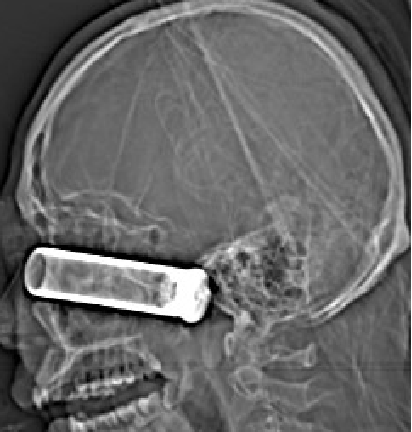

患者,男,31岁

外伤致左眼出血、疼痛4小时余入院

NS:神清,对答好,左侧眼内容物缺失,左上眼睑可见长约4cm外伤伤口,眼内可见金属异物,右侧瞳孔直径3mm,对光反射正常,眼前2m指数;四肢活动可,肌张力正常,生理反射存在,病理反射未引出。

2014-9-29 CT